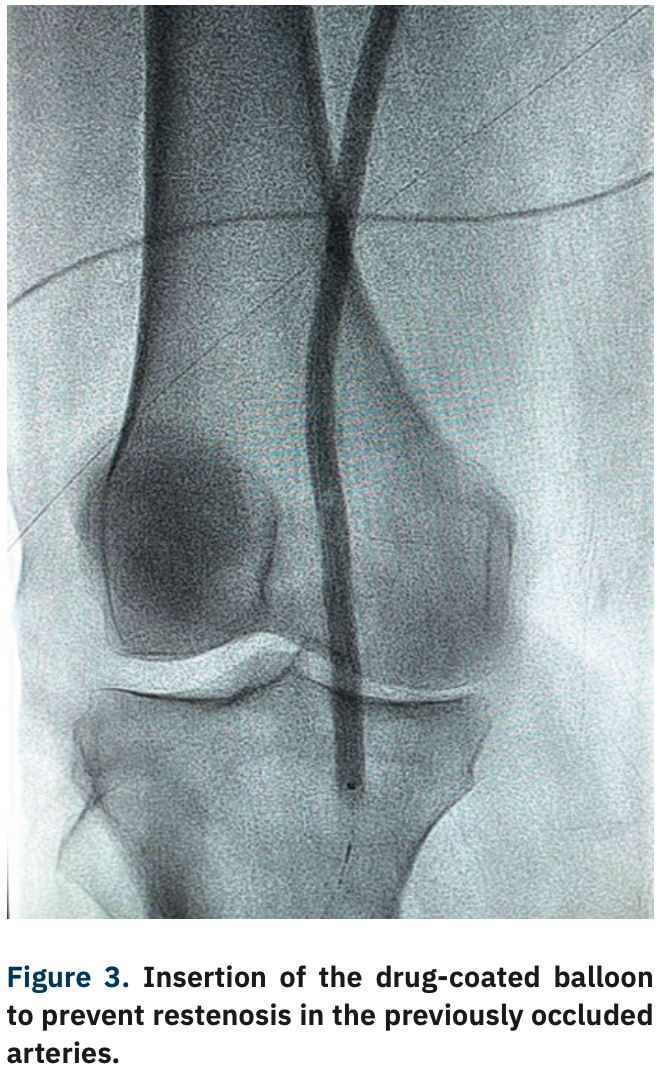

Contralateral retrograde access of the left femoral artery was obtained, and a 6 French (Fr) 45 cm sheath was advanced to the level of the right common femoral artery (CFA). A Mongo wire (Asahi Intecc) was inserted to cross the distal SFA and popliteal lesions. An embolic protection device (EPD) filter was placed in the distal popliteal artery (Figure 2). Orbital atherectomy was performed with a 1.5 solid crown Diamondback (CSI), followed by a 5 mm x 250 mm drug-coated balloon at the lesioned sites (Figure 3).